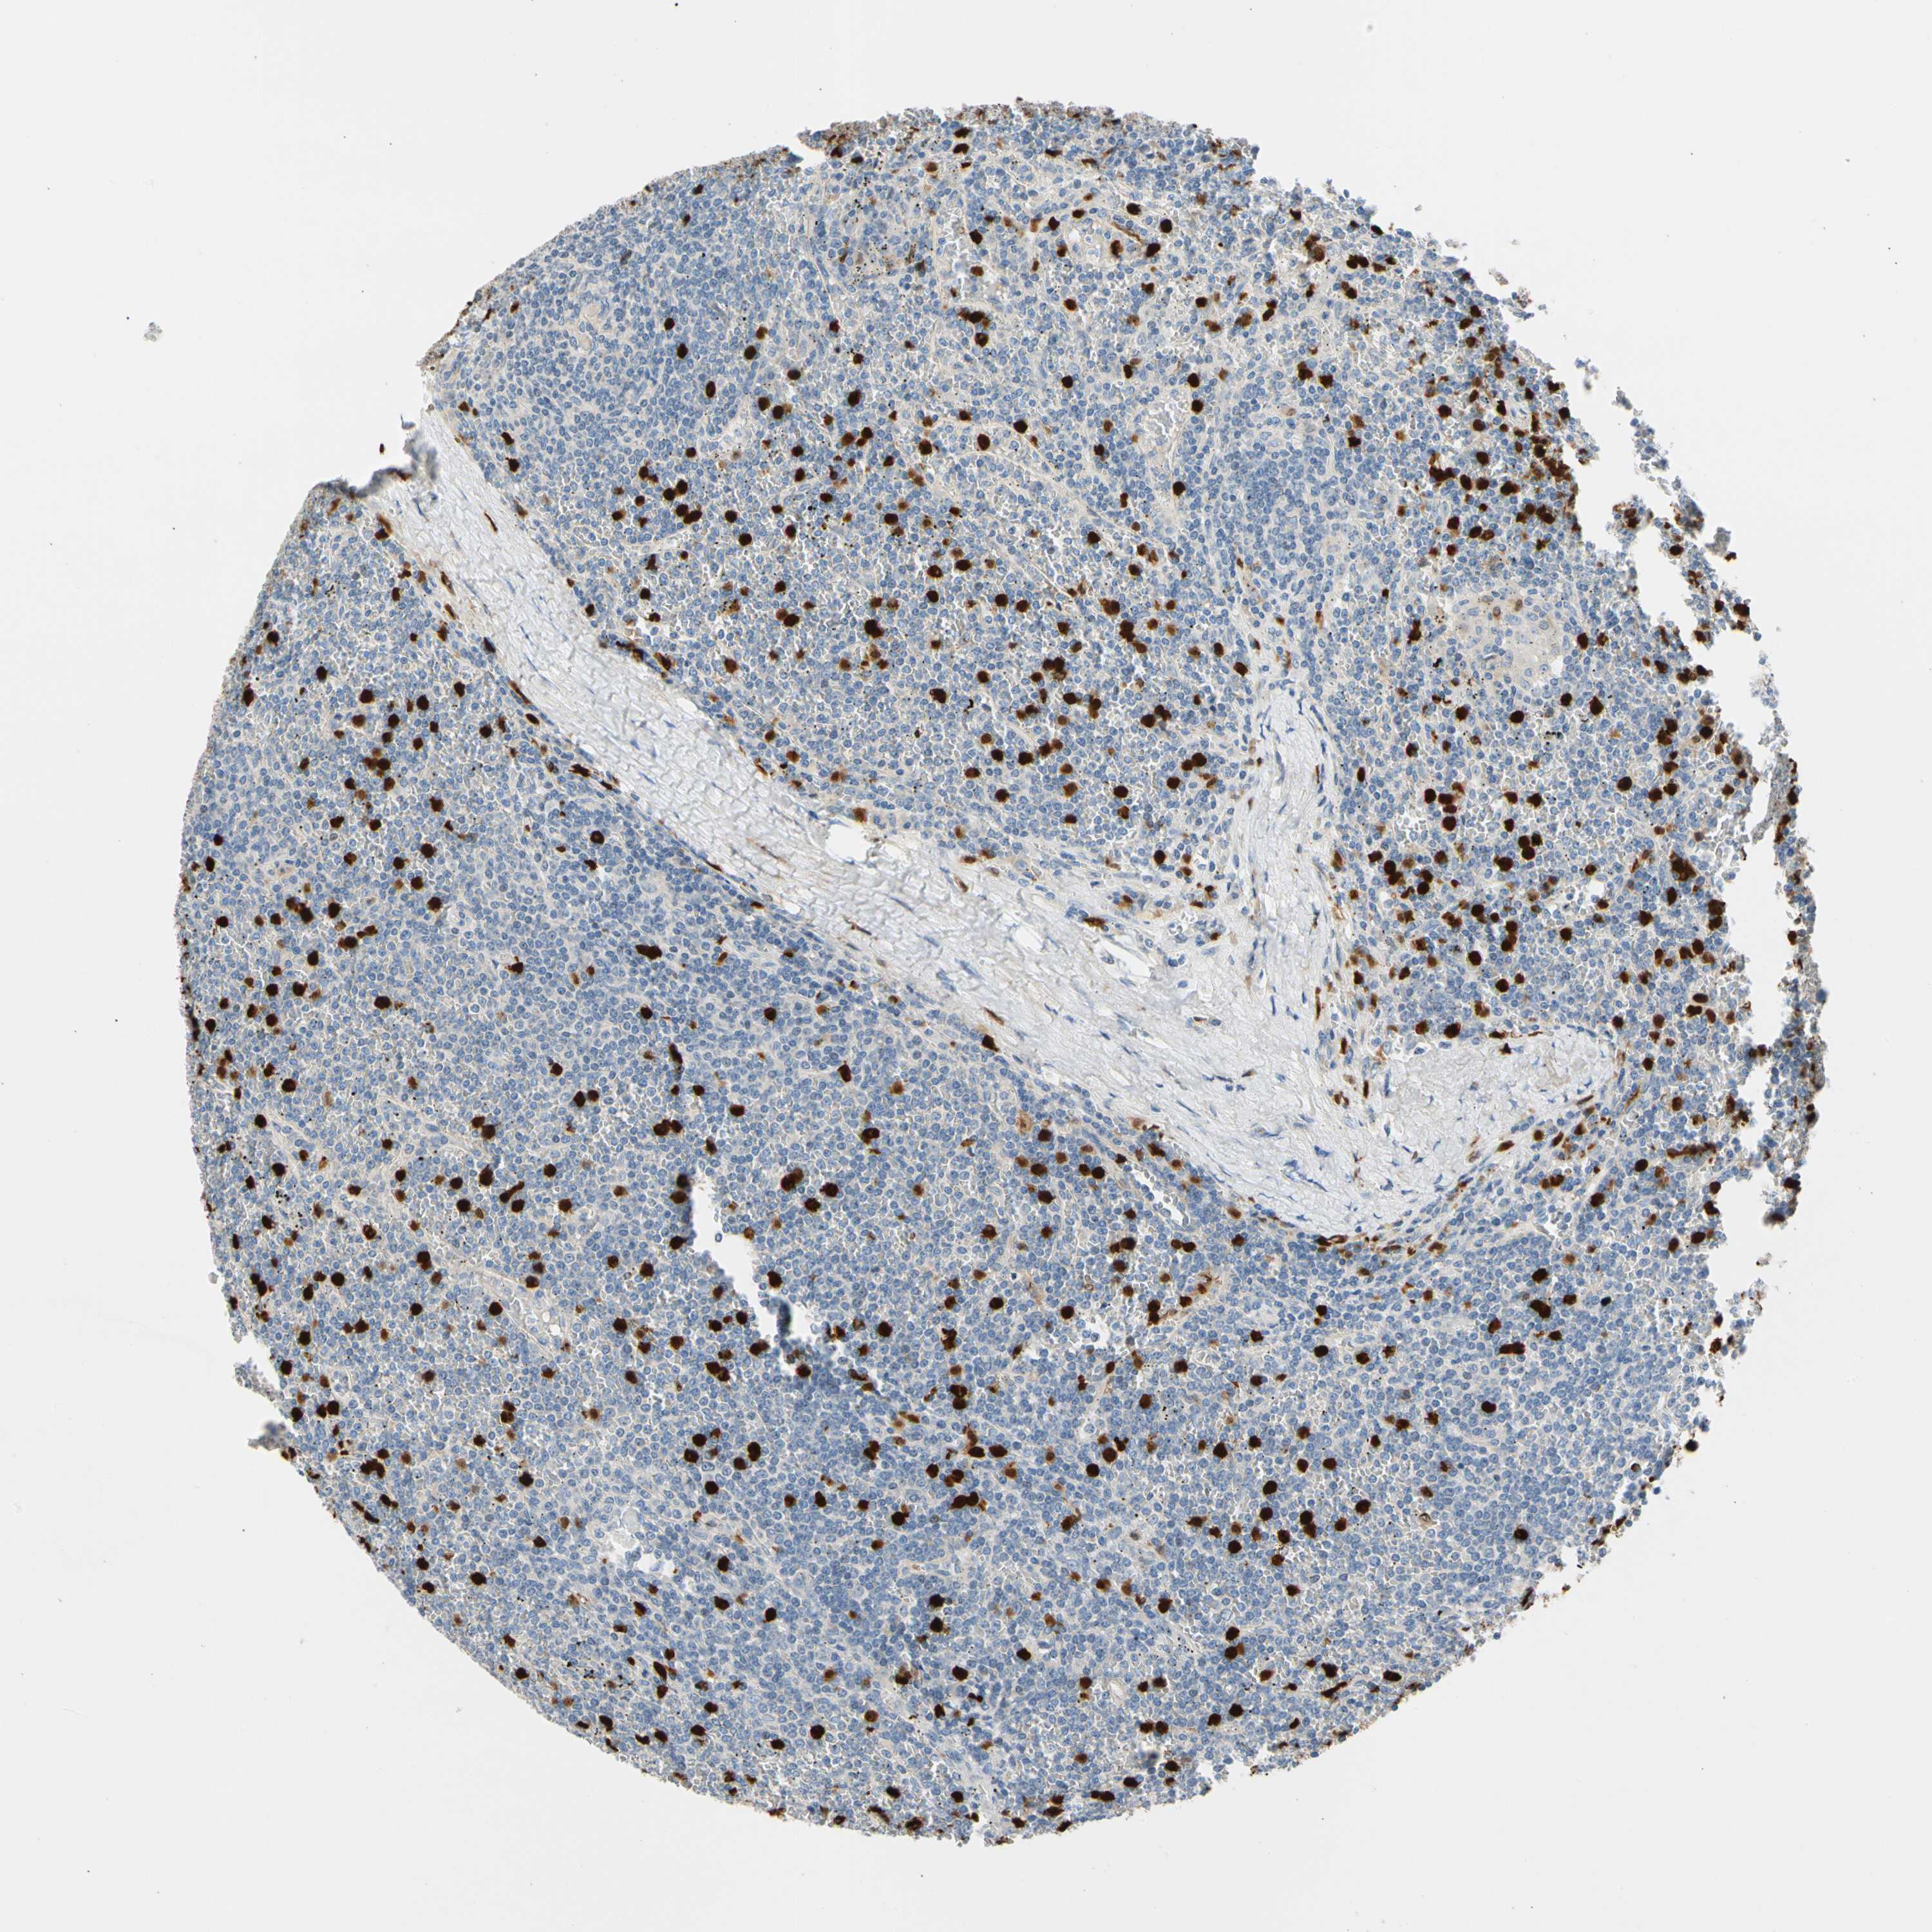

CANCER LYMPHOMA Show tissue menu

LYMPHOMA - Protein expressioni

A mouse-over function shows sample information and annotation data. Click on an image to view it in a full screen mode. Samples can be filtered based on level of antibody staining by selecting one or several of the following categories: high, medium, low and not detected. The assay and annotation is described here.

Antibody stainingi

Antibody staining in the annotated cell types in the current human tissue is reported as not detected, low, medium, or high, based on conventional immunohistochemistry profiling in selected tissues. This score is based on the combination of the staining intensity and fraction of stained cells.

Each image is clickable and will lead to virtual microscopy that enables deeper exploration of all samples and also displays staining intensity scores, fraction scores and subcellular localization as well as patient and tissue information for each sample.

Antibody HPA008052

Antibody CAB010277

Staining

High

Medium

Low

Not detected

Intensity

Strong

Moderate

Weak

Negative

Quantity

>75%

75%-25%

<25%

None

Location

Nuclear

Cytoplasmic/membranous

Cytoplasmic/membranous,nuclear

Hodgkin's disease, NOS

Malignant lymphoma, non-Hodgkin's type, Low grade

Malignant lymphoma, non-Hodgkin's type, High grade